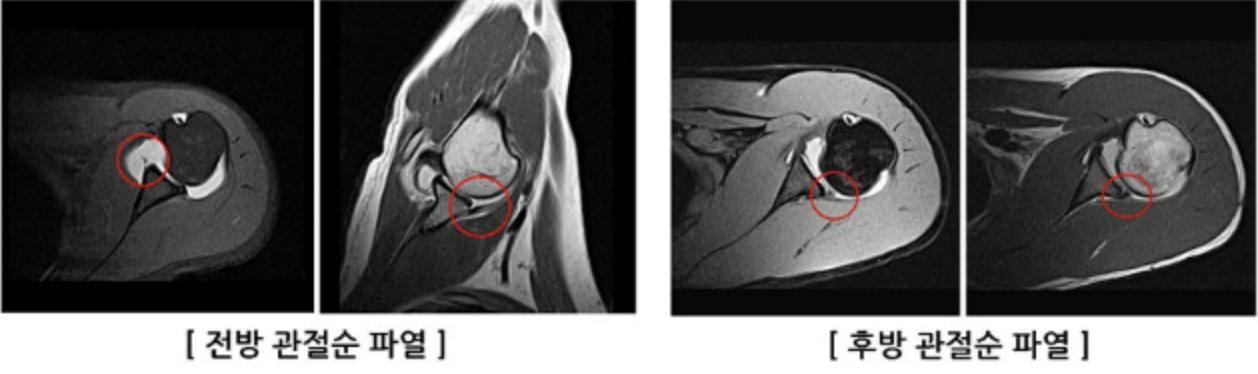

앞·뒤 관절테두리(관절순) 파열은 어깨 관절오목 앞·뒤 테두리가 찢어져, 어깨가 빠질 듯한 느낌이나 실제 탈구·반탈구가 반복되기 쉬운 상태를 말한다.

- 관절오목 앞쪽(전방) 또는 뒤쪽(후방)을 둘러싼 관절테두리가 외상·탈구·반복된 스트레스로 찢어지거나 벗겨진 상태이다.

- 전방 파열은 전방 불안정성과, 후방 파열은 후방 불안정성과 밀접하게 연관된다.